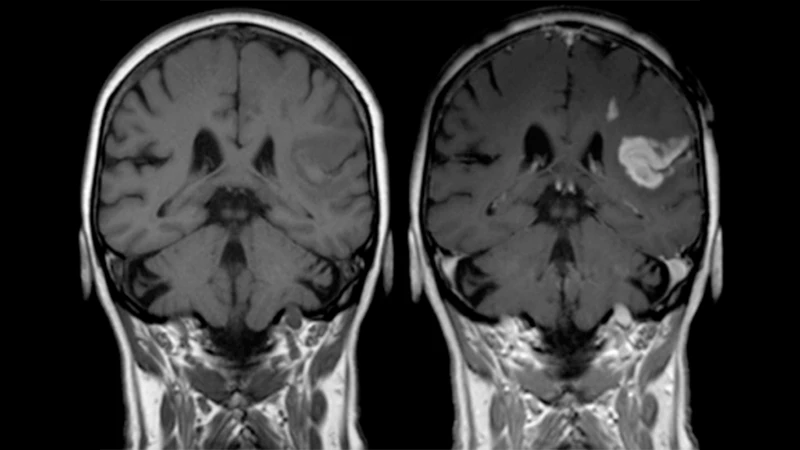

2. To Characterize Tumors and Masses

Many tumors, both cancerous and benign, develop their own unique blood supply. How a mass "enhances"—or lights up—after contrast injection gives the radiologist important clues about what it might be. Some patterns of enhancement are characteristic of specific types of tumors, helping to guide the diagnosis.

An MRI of a brain showing a brightly enhancing tumor after the administration of gadolinium contrast.